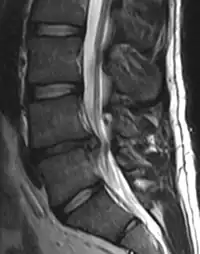

- Magnetic resonance imaging is the gold standard study for confirming a suspected LDH. With a diagnostic accuracy of 97%, it is the most sensitive study to visualize a herniated disc due to its significant ability in soft tissue visualization. MRI also has higher inter-observer reliability than other imaging modalities. It suggests disc herniation when it shows an increased T2-weighted signal at the posterior 10% of the disc. Degenerative disc diseases have shown a correlation with Modic type 1 changes. When evaluating for postoperative lumbar radiculopathies, the recommendation is that the MRI is performed with contrast unless otherwise contraindicated. MRI is more effective than CT in distinguishing inflammatory, malignant, or inflammatory etiologies of LDH. It is indicated relatively early in the course of evaluation (<8 weeks) when the patient presents with relative indications like significant pain, neurological motor deficits, and cauda equina syndrome. Diffusion tensor imaging is a type of MRI sequence used for detecting microstructural changes in the nerve root. It may be beneficial in understanding the changes that occur after herniated lumbar disc compresses a nerve root, and might help in differentiating the patients that need surgical intervention. In patients with a high suspicion of radiculopathy due to lumbar disc herniation, yet the MRI is equivocal or negative, nerve conduction studies are indicated.[43] T2-weighted images allow for clear visualization of protruded disc material in the spinal canal.

Example of a herniated disc at L5–S1 in the lumbar spine